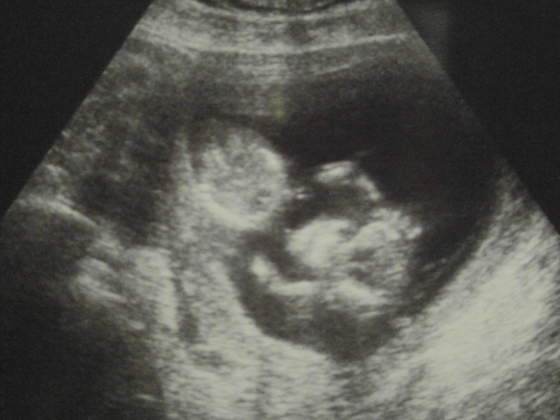

08.06/04.10/09.13

Ja też dzisiaj u ginki byłam. Mam się oszczędzać, taaa. Oczywiście pessar mnie nie ominie, liczyłam się z tym, ale myślałam, że jeszcze nie będzie na ten temat

Kolejna wizyta 14.03.